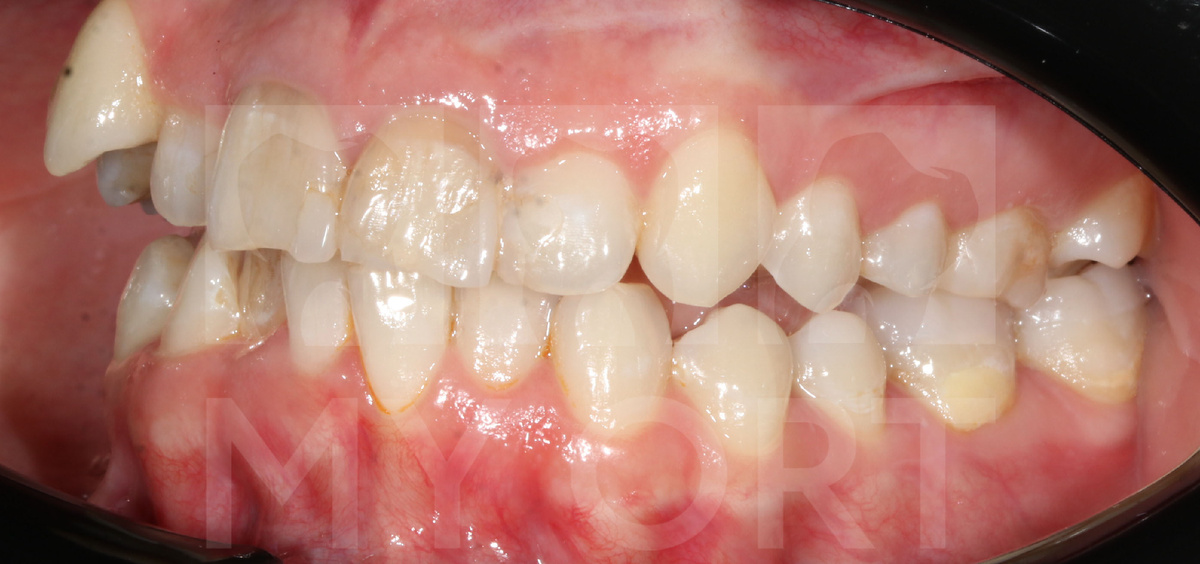

Пациентка обратилась ко мне с выраженными болями в области височно-нижнечелюстного сустава. Она жаловалась на дискомфорт при жевании, болезненные ощущения при движении нижней челюстью и ощущение усталости мышц. Кроме этого, ее беспокоила скученность зубов и неэстетичное положение верхнего правого клыка.

Также была обнаружена значительная скученность зубов, отсутствие места для прорезывания 13-го зуба и ранее перенесенная дисфункция височно-нижнечелюстного сустава, которая требует строгого функционального подхода.

3. Устранена скученность зубов.

4. Была достигнута эстетика зубов и улыбки.